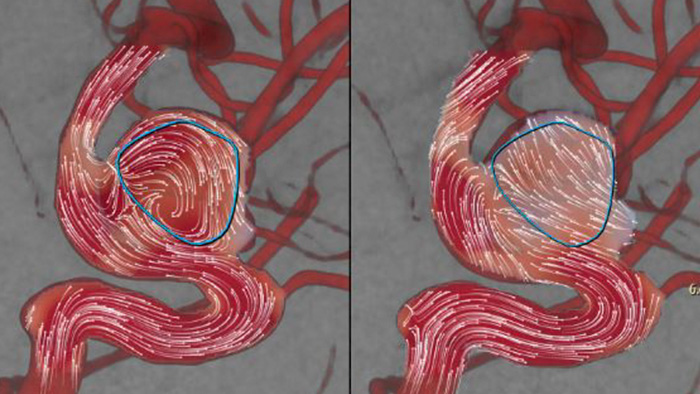

AneurysmFlow is ontworpen om u relevante informatie te geven voor en na de implementatie van de flowdiverter. Het visualiseert en kwantificeert flowveranderingen voor meer vertrouwen in de procedurele effectiviteit.